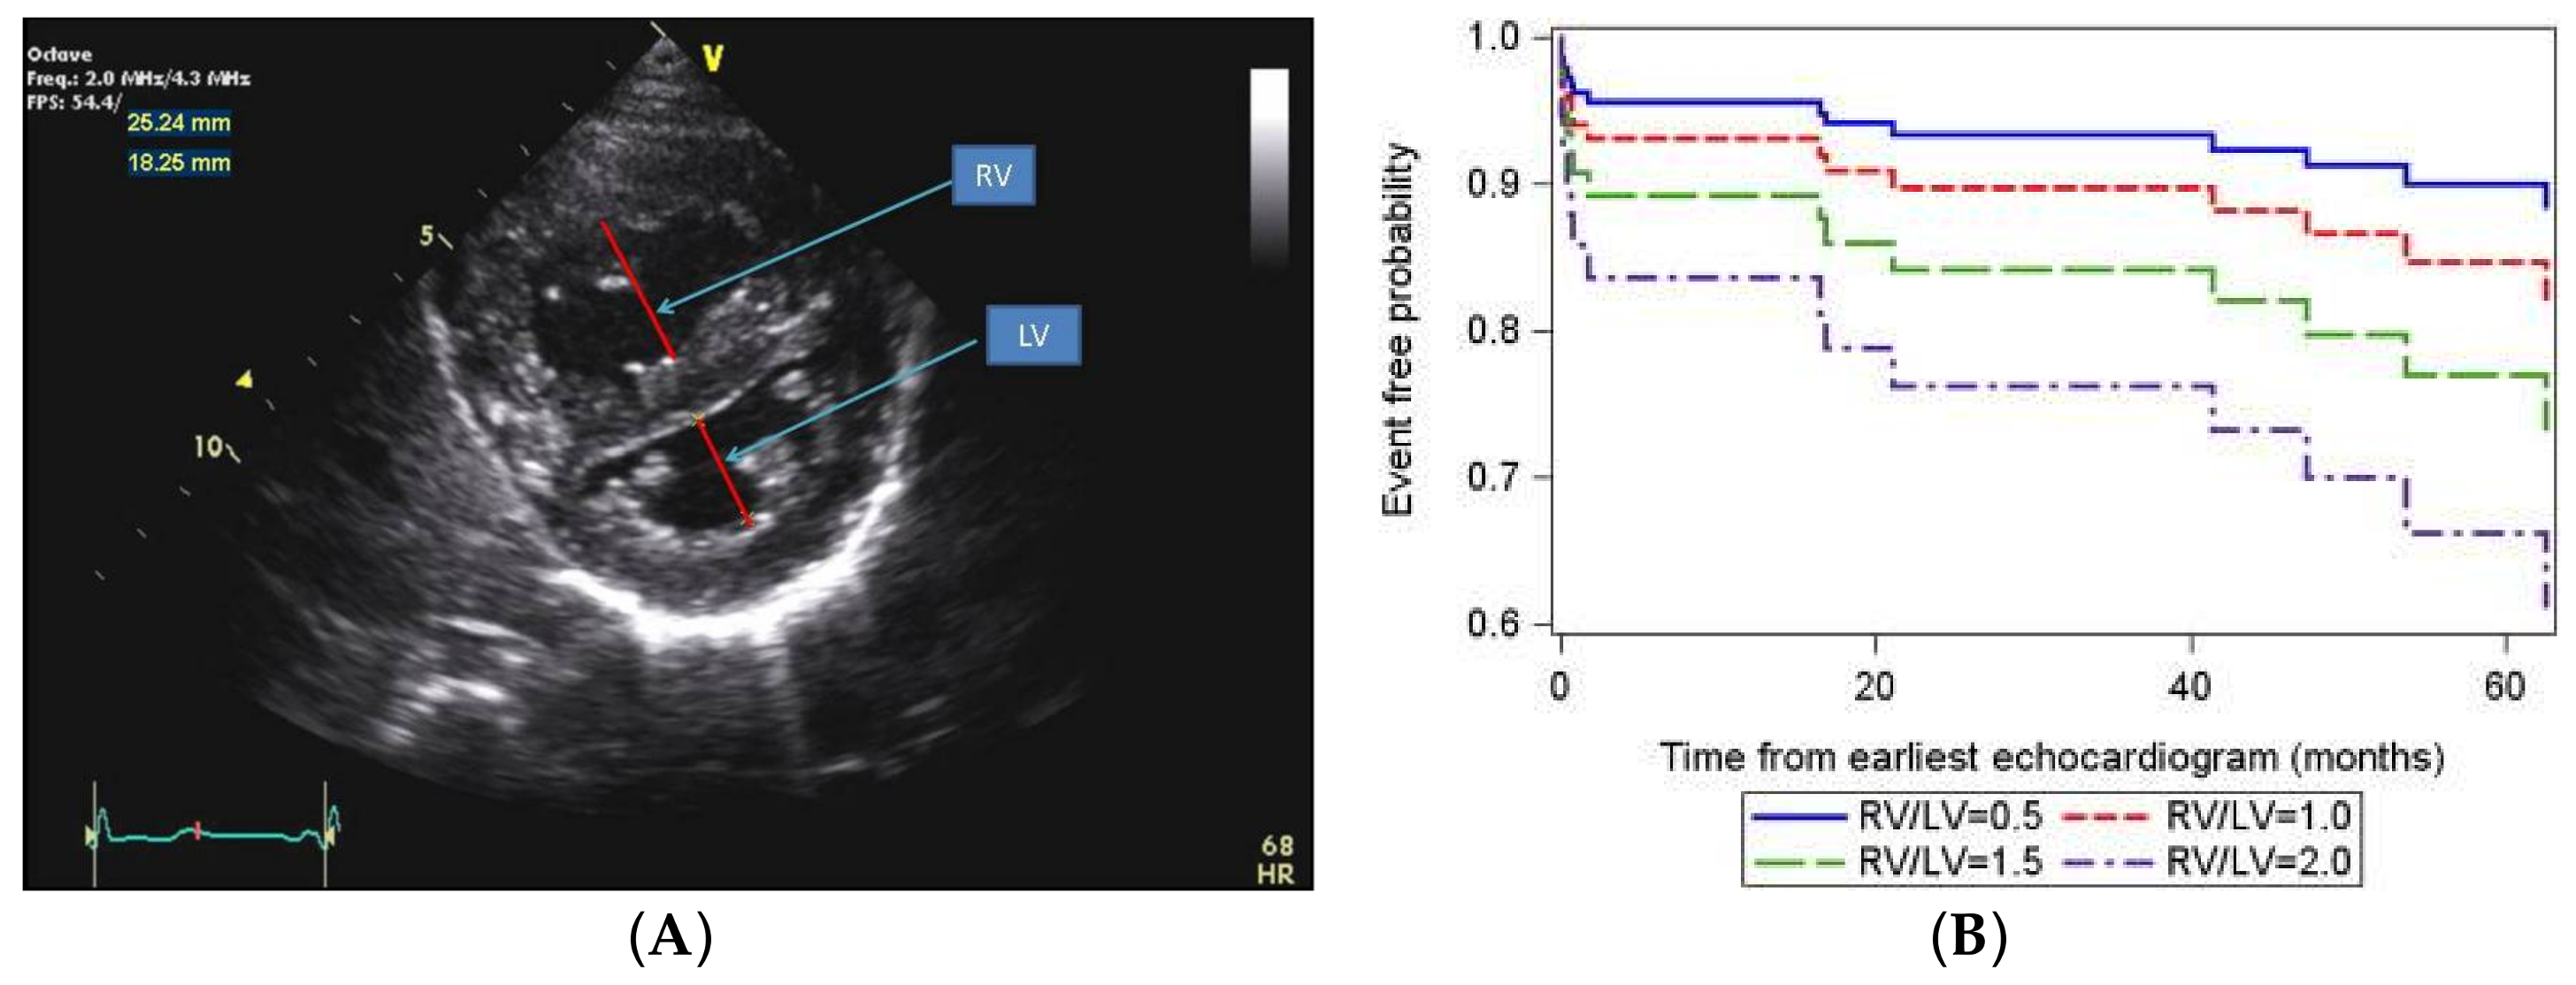

Recent data have additionally identified echocardiographic markers that can be used to track disease severity and, in some cases, predict clinical outcomes [65]. The ratio of right ventricle to left ventricle (LV) size at end systole is a strong predictor of outcome (Figure 6) [66]. An increasing RV/LV systolic ratio is associated with an increasing hazard for a clinical event (hazard ratio, 2.49; 95% confidence interval, 1.92–3.24). The presence of a pericardial effusion is rare in children, but when present, suggests a poor prognosis [62,67]. As PAH progresses and RV function worsens, the systolic portion of the cardiac cycle lengthens leading to an increase in the systolic to diastolic ratio. The S/D ratio is higher in PAH patients than in controls (1.38 +/− 0.61 vs. 0.72 +/− 0.16, p < 0.001), and is associated with worse echocardiographic RV fractional area change, worse catheterization hemodynamics, shorter 6-min walk distance, and worse clinical outcomes independent of pulmonary resistance or pressures (Figure 7) [68,69,70]. Tissue Doppler imaging (TDI) directly measures myocardial velocities and has been shown to be a good measure of RV and LV systolic and diastolic function. In recent pediatric studies, right ventricular TDI velocity was lower in children with PAH compared to healthy controls [71,72] Moreover, tricuspid diastolic velocity (E’) had a significant inverse correlation with right ventricular end-diastolic pressure and mean pulmonary arterial pressure. Cumulative event-free survival rate was significantly lower when tricuspid E’ velocity was ≤8 cm/s (log-rank test, p < 0.001, Figure 8) [72]. As the right ventricle contracts primarily in a longitudinal fashion, RV longitudinal strain is a powerful tool to predict clinical outcome in adults with PAH [73]. Its role in evaluating pediatric patients with PAH remains incompletely understood. Finally, function assessment by 3-dimensional echocardiography correlates well with cardiac MRI in children with congenital heart disease [74] and is being evaluated in children with pulmonary hypertension.

Figure 6.

(A) Parasternal short axis view of the right and left ventricles (RV/LV) at the level of the papillary muscles. The RV/LV ratio is derived from RV diameter and LV diameter at end-systole. RV/LV end-systolic ratio is predictive of outcome; (B) Estimated survival curves for four possible RV/LV ratios estimated from the Cox varying coefficients regression corresponding to a hazard ratio of 2.49 for RV/LV ratio [66].